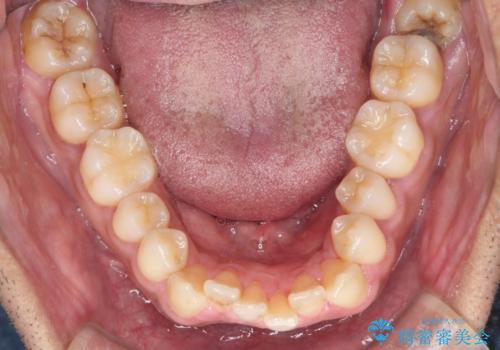

上はワイヤー部分矯正、下はインビザラインの部分矯正コースを行いました。

インビザラインだけでも治療は可能ではあると思いますが、ライトパッケージでは難しいと思います。

また、入れ替えを行う間左上の前歯だけで咬まなくてはならない状況になるため、マウスピース矯正単独で行うと時間がかかり、最悪神経が失活することもありますのでワイヤーがお勧めです。